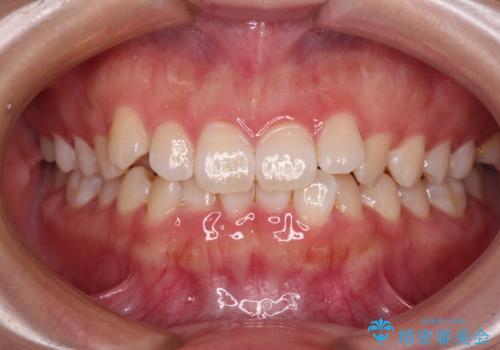

[ マウスピース矯正 ] 出っ歯に見える前歯を改善したい

![[ マウスピース矯正 ] 出っ歯に見える前歯を改善したいの症例 治療前](https://seimitsushinbi.jp/wp/wp-content/uploads/2023/10/IMG_6858-500x350.jpg?v=1697014973)

![[ マウスピース矯正 ] 出っ歯に見える前歯を改善したいの症例 治療後](https://seimitsushinbi.jp/wp/wp-content/uploads/2023/10/8a6c9bf89570c0c75da0a5fabd1cd70e-500x350.jpg?v=1697014858)